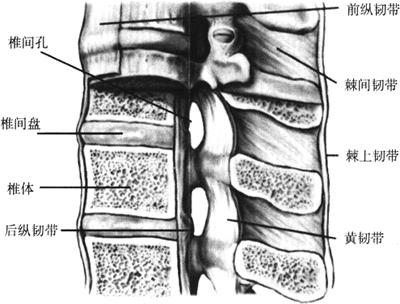

脊柱连接由韧带、椎间盘及椎间关节构成(图1-25)。

图1-25 脊柱的连接

(一)前纵韧带(anterior longitudinal ligament)

前纵韧带位于椎体前面。上端起自枕骨底部和寰椎前结节,向下韧带纤维延伸,途经各椎体前面,止于第1或第2骶椎前面。前纵韧带为人体最长的韧带。其宽度和厚度在各个不同部位有明显差异,在颈椎和腰椎及其椎间盘部较阔,但略薄;而胸椎节段较窄且厚。前纵韧带系由浅层、中层和深层等3层并列的纵形纤维组织而成。浅层纤维较长,通常跨越3~4个椎体;中层纤维略短,可跨越2~3个椎体;深层纤维最短,仅连接相邻两个椎体。

前纵韧带与椎体和椎间盘关系在不同部位紧密程度也不尽一致。通常,纵韧带在椎体水平与椎体之间较疏松,而与椎体边缘和椎间盘连接紧密,紧贴其表面。3层纤维共同作用维持椎体前方的稳定性,具有较强的张应力。同时前纵韧带有防止椎间盘向前突出和限制脊柱过度后伸的作用(图1-25)。

(二)后纵韧带(posterior longitudinal ligament)

后纵韧带位于椎管前壁内面,即椎体后部,较为薄弱、细长,但较紧韧。自第1颈椎椎体后面,向上方移行于覆膜,向下方沿各椎节的椎体后缘,直达骶骨,并移行于骶尾后深韧带。后纵韧带的宽度和厚度在各节段不同,颈椎、上胸椎及其椎间盘部较宽阔,下胸椎和整个腰椎节段相对较窄。该韧带有分3层和两层之看法,但通常将其分为两层。浅层纤维连续跨越3或4个椎节,而深层纤维呈“八”字形,仅连接相邻两个椎节。深层韧带纤维之边缘部分紧靠近椎弓根(图1-49)。

(三)黄韧带(ligament flava)

黄韧带系由薄而坚韧的黄色弹性纤维构成,故名。该韧带主要部分位于椎板间又称椎板间韧带或弓间韧带。黄韧带呈膜状,成节段性结构。黄韧带向上附着于上位椎弓板下缘的前面,向下附着于下位椎弓板上缘的后面,薄而较宽,犹如屋瓦叠掩。黄韧带前面凹陷、光滑,正中部有一裂隙,其间有少量脂肪组织,并伴有静脉通行。黄韧带为弹性结缔组织膜,后中央部与棘间韧带相连,向外至关节突关节内侧缘,向外侧扩展部附着于横突根部,同时近关节处与关节囊相融合参与形成关节囊(图1-25、图1-49)。黄韧带有一定弹性,脊柱屈曲时,可随相邻椎弓板稍伸展;过伸时可稍缩短,而不致发生皱褶突入椎管内。

(四)棘上韧带(supraspinal ligament)

棘上韧带系由项韧带向下至第7颈椎棘突开始,为一细长、坚韧的条束状带,附着于椎节棘突尖部,止于骶骨的骶中嵴。两侧与背部筋膜相连续,其前方与棘间韧带相愈合,界限很难分开。在不同节段上,棘上韧带的宽窄与厚度不一样。胸椎段呈条索状并较薄,腰椎宽厚坚韧。该韧带纤维可以分为浅层、中层和深层。浅层纤维通常跨越连续3~4个椎节的棘突尖,中层可跨越2~3个椎节,而深层纤维仅连接两个椎节棘突之间。浅层纤维具有充足的弹性,强于中层和深层。成人腰椎的棘上韧带具有很强的张应力,其功能作用与棘间韧带及腰背筋膜相一致;其退变可能发生软骨化,或有撕裂、囊性变,偶尔缺如。

(五)棘间韧带(interspinal ligament)

棘间韧带薄而无力,位于相邻椎节的棘突之间。在一节段水平,该韧带沿棘突基底道棘突尖,充盈棘突间。韧带的前部与黄韧带中央裂隙部相贴,后部逐渐移行于棘上韧韧带。颈椎和上胸椎棘间韧带发育欠佳,较松弛薄弱;腰椎厚而坚韧,发育相当完善。从纤维分层解剖来看,L1~L2、L2~L3和L3~L4可分为4层;L4~L5与L5~S1的棘间韧带分为3层。